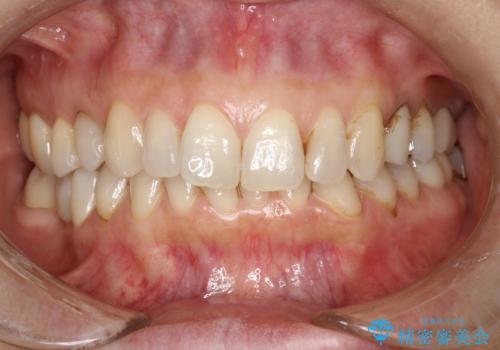

PMTCで歯と歯の間の細かいステインの除去

- 歯磨きでは取れない歯と歯の間の汚れが気になるとのことで来院されました。PMTC60分コースを行いました。

PMTCは、歯に付着した汚れを除去していくため、着色が気になる場合にも行うことができます。ご自身でのセルフケアだけで着色を落とそうとすると、逆に歯を傷つけてしまったり、精密に汚れを除去できないこともあります。また、日常生活で着色しやすい飲食物を避けたりすることはストレスに感じてしまったり、あまり現実的ではありません。

毎日丁寧に歯磨きをしていても、日常生活での飲食物などにより着色してしまうことはあります。PMTCでは、歯の表面の凸凹にミネラルを補給して、ツルツルの表面に仕上げます